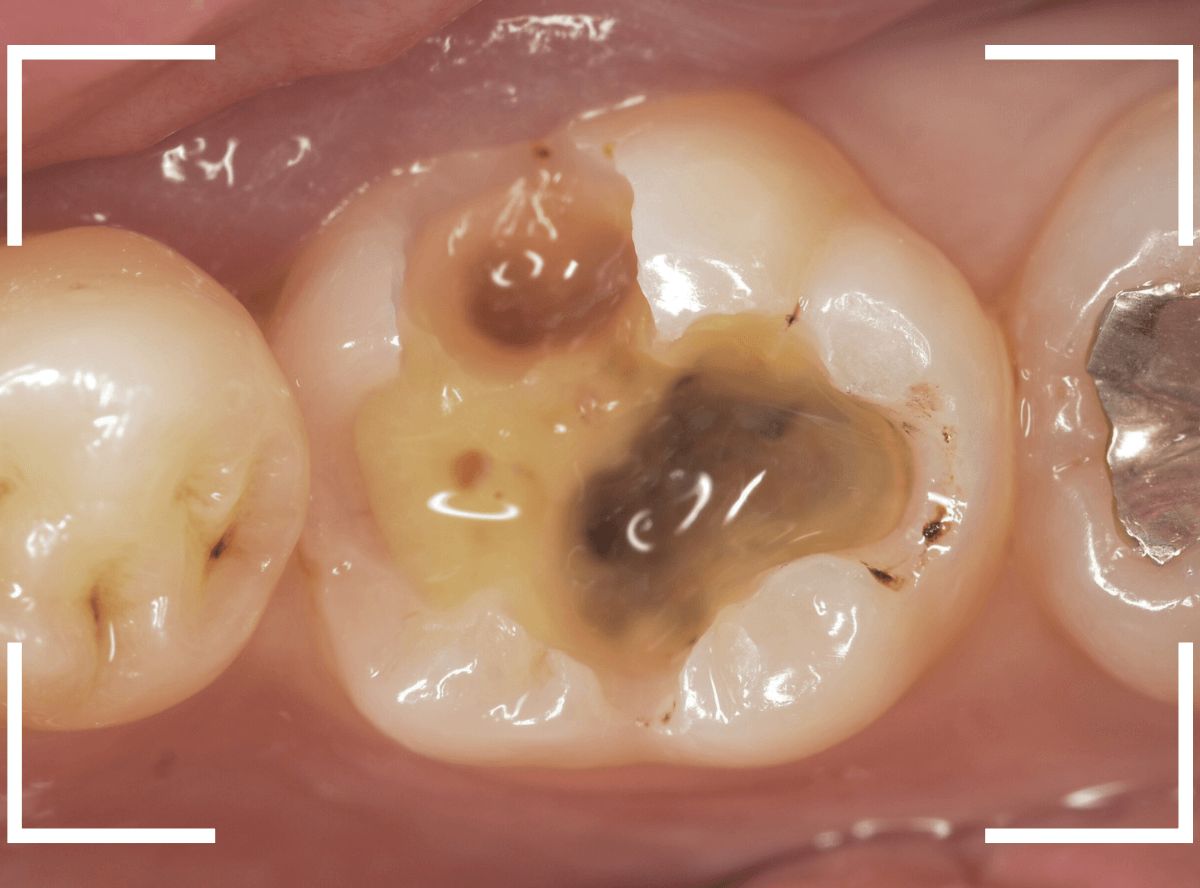

Case.18 虫歯なのは間違いないが、境界がはっきりしない

「つめものが外れて、噛むと痛い」という訴えで来院された患者さんさんです。

一見で、表面が虫歯になっているのと、レジンが劣化しているのがわかります。

レントゲン写真で確認します。

〇部が当該の歯です。

症状もあるので、虫歯が深そうですが、全体がもやっとして、どこからどこまで虫歯なのかはっきりわかりません。

まれに、こんな時もあります。

レジンを外し、虫歯の処置を進めます。

慎重に虫歯を除去し、一安心か、という寸前で(〇部、小さく出血しているところ)露髄してきました。

神経を除去しないとダメかもしれません。。。

神経を保護するお薬をつめて、経過観察します。

痛みが出ませんように。。。